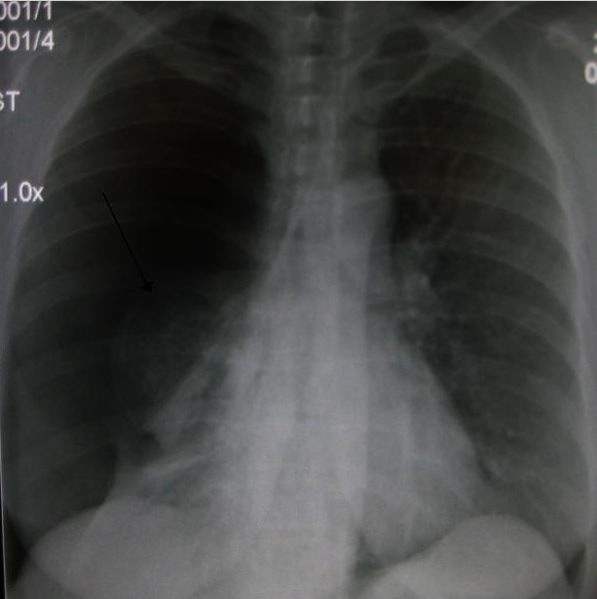

Để chẩn đoán xác định xẹp phổi và tìm nguyên nhân, bác sĩ có thể chỉ định một số xét nghiệm như: